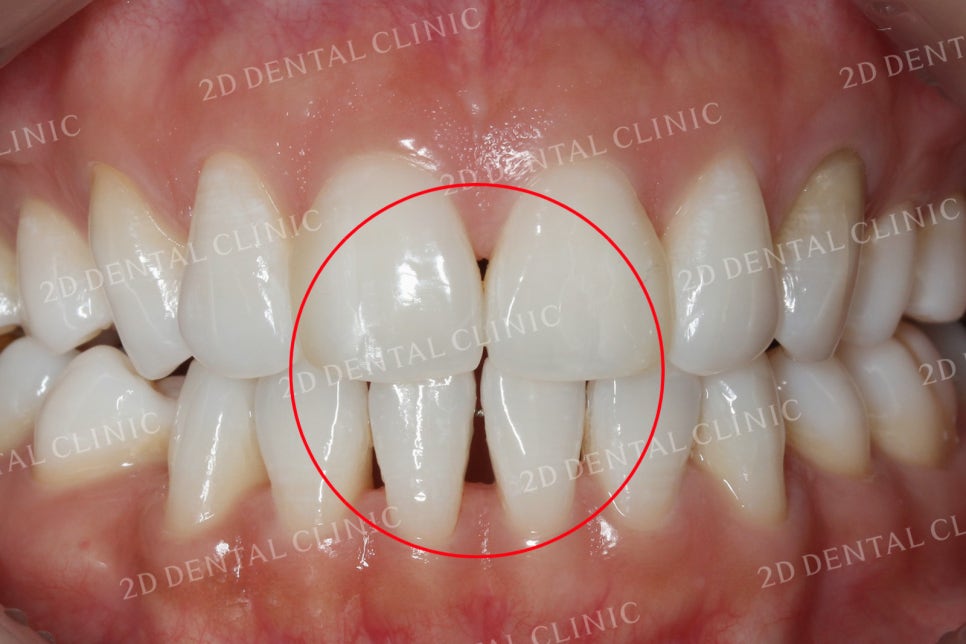

상하악 교합 시 사진입니다.

쎄라필름은 치아 사이의 틈새는 물론,

누렇게 착색된 치아의 색상과

일정하지 않은 형태와 크기 등을

환자분이 원하시는 방향으로

시술하실 수 있습니다.

상악의 사진을 보시면

중절치 사이에서 보이던

블랙트라이앵글이

말끔히 사라진 모습입니다.